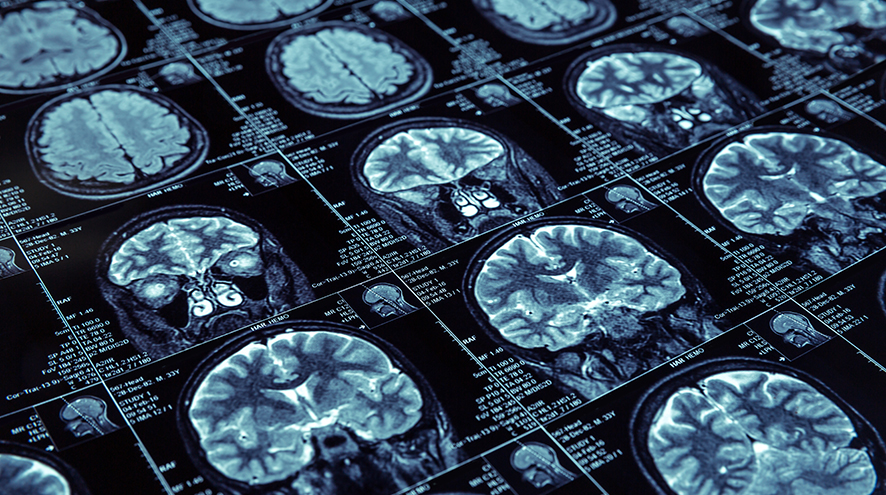

MRI images.

Did you know that someone in the world develops dementia every three seconds? And the number of people living with dementia globally is predicted to triple by 2050, rising to 152 million.